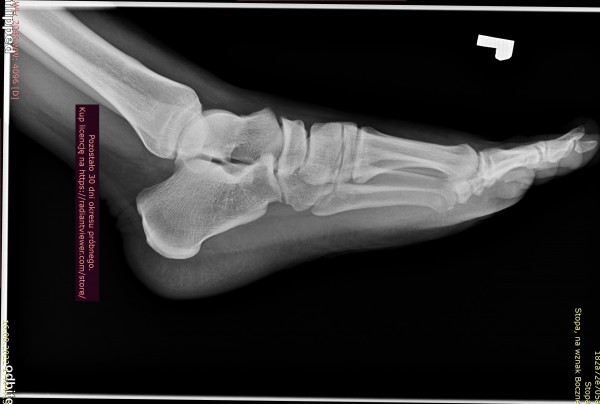

Rok temu poszedłem do ortopedy z bolem piety. Nie robil zadnych zdj RTG czy usg tylko wyslal na rehabilitacje bo wydawało mu się, ze to ostroga piętowa. Po rehabilitacji bol minal dopiero po ok 2 msc a, ze byla zima to i mobilnosc mniejsza mniej sportu wiec bol ustal. Na wiosne zaczalem jezdzic na rowerze plus granie w pilke na orliku. Bylo ok az do ubieglego tygodnia. Bol piety powrocil. Zrobilem prywatnie rtg, jednak opis bede mial dopiero za tydzien. Czy na zalaczonym zdjeciu widac ostroge lub cos innego niepokojacego przez co moze mnie boleć ?

edit. Dodam, ze boli mnie przy dotyku rowniez nad kostka ok 5-8cm wyzej jakby achilles prawdopodbnie po kopnieciu w noge.